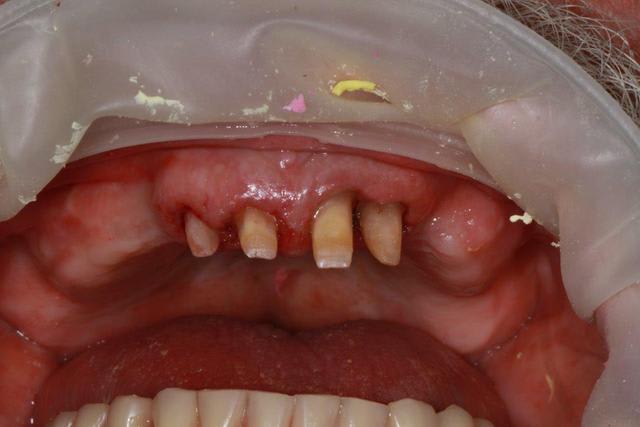

ce n'est pas un cas où je cherches une solution mais un cas fini.

Le patient, viens de lui même, après avoir été suivi par plusieurs confrères qui devant son traitement (BP) lui ont formellement déconseillés les implants.

Le problème, c'est que les implants ne sont pas formellement déconseillés avec les BP, par contre les extractions posent problème.

Or il fallait enlever 34/35 et 44/45...ce que j'ai fait avec précaution, nettoyage soigneux éponges de gelatemp et sutures.

8 jours après, cicatrisation nickel, donc je n'hésite pas pour les implants à la mandibule, et je propose un partiel maxillaire avec conservation des incisives....